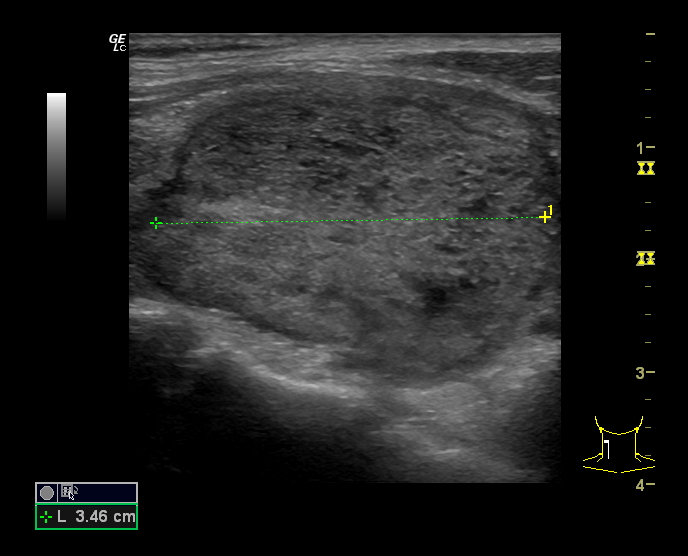

Hallazgos ecográficos

Se estudia la glándula tiroidea mediante sonda lineal de alta frecuencia, realizando cortes transversales y longitudinales. A nivel del lóbulo tiroideo derecho se objetiva un nódulo sólido, con forma «más ancho que alto», isoecoico, con zonas heteroecoicas de 2,4 x 3,4 cm (figura 1), que presenta una lobulación en su margen interno (figura 2), con halo periférico incompleto y vascularización mixta, principalmente periférica (figura 3). No se observan calcificaciones ni adenopatías patológicas. Adyacente al mismo, otro nódulo milimétrico (figura 4), de similares características.